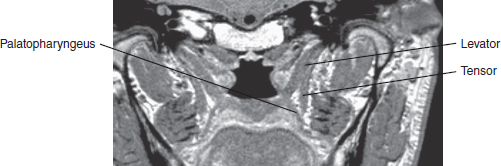

50 ○ Cleft palate repair is the most important component of cleft surgery, because it determines the speech and communication outcome and potentially has the greatest effect on maxillary growth and dental arch relationship and probably also on hearing. ○ Some cleft palates (particularly in certain syndromes) are undoubtedly hypoplastic. However, all cleft palates have abnormal anterior insertion of the palate muscles, particularly the levator veli palatini (the levator). ○ The term intravelar veloplasty has been used to describe an attempt to correct the muscle abnormality. However, this means different things to different surgeons. ○ The technique involving dissection between the oral mucosa and muscle and between the nasal mucosa and muscle and then retropositioning and reconstruction of the palate muscles. This is best done using an operating microscope. ○ Wherever possible, the palate should be closed without lateral releasing incisions. Whether this is possible depends on the type, extent, and width of the cleft. ○ Speech assessment is the prime outcome measure, but it is very difficult to compare between centers because of the lack of consensus criteria among countries and across languages. Ideally, speech should be blindly assessed by external speech pathologists. ○ Both the eventual outcome and the burden borne by patient and parents to achieve this outcome need to be considered. Cleft palate repair is the most important component of cleft surgery; it determines the patient’s speech and communication outcome and potentially has the greatest effect on maxillary growth and dental arch relationship.1 The primary aims of cleft palate repair are to improve feeding, to achieve normal speech, and to minimize adverse effects on maxillary growth. The technique of palate repair may also have an effect on middle-ear function and hearing. Victor Veau2 described the abnormal palatal muscle anatomy in a cleft palate. From his observations, Veau concluded that speech outcomes could be improved by early palate repair. Braithwaite3 and later Kriens4 proposed surgical techniques to correct the abnormal anatomy of the velar musculature. Others believed that velar function could be improved by palatal pushback.5–7 However, evidence now suggests that push-back techniques are damaging to maxillary growth.1,8 My technique, as described here, began in 1974 with attempts to manage patients who had velopharyngeal dysfunction after palate repair by rerepair with muscle dissection and reconstruction, rather than through the use of traditional pharyngeal flaps or pharyngoplasties. Evidence of improvement in palate function after rerepair encouraged attempts to correct the muscle malposition in primary cleft palate repair.9,10 The technique has evolved over 40 years (Fig. 50-1). Fig. 50-1 The evolution of a cleft palate repair technique. Each of these developments has made the procedure more precise and easier to perform. The technique was first reported after 25 years of evolution.11 Whenever possible, the procedure should be carried out under an operating microscope, which greatly improves visualization of the anatomy and increases the safety and reliability of the operation.12 Because of the long learning curve and potential for doing significant harm, this procedure is not appropriate for the occasional operator. Rates of velopharyngeal dysfunction after palatal repair have been reported to range from 4% to 70%. Differences in reporting protocols make such figures unreliable. However, no technique will produce a velopharyngeal mechanism that is competent throughout life in every patient; the palate is short in many patients with clefts.13 The palatal tissues (particularly in patients with certain syndromes) are undoubtedly hypoplastic. All cleft palates have abnormal insertion of the palatal muscles, particularly the levator veli palatini (the levator). This muscle is always oriented sagittally in patients with palatal clefts and inserts abnormally into the cleft margin in the anterior half of the velum. The levator itself does not insert into the back of the hard palate, as commonly described. The term intravelar veloplasty has been used to describe surgical procedures that attempt to correct the muscle abnormality.4 However, this term means different things to different surgeons.14 My technique involves dissection between the oral mucosa and muscle and between the nasal mucosa and muscle, then retropositioning and reconstructing the palatal musculature. Cutting et al15 independently developed a technique that bears some similarities to that described here, but with several major differences. An ingenious alternative approach to correct the muscle abnormality is the double-opposing Z-plasty technique described by Furlow,16 wherein the muscles are retrodisplaced, attached on one side to the oral mucosa and on the other side to the nasal mucosa. This procedure has the theoretical advantage of also lengthening the soft palate by narrowing it, because it has to expand transversely as well as longitudinally with elevation. The Furlow palatoplasty is an asymmetrical procedure, and asymmetry of function has been observed (P. Chen, personal communication, 2011). Despite this, the procedure has many strong advocates. However, the Furlow technique may be difficult to perform in wide clefts and is difficult to revise. Very satisfactory results have been reported by many surgeons. However, good comparative data, comparing this approach to radical muscle correction are not available. The technique is described in detail in Chapter 49. I have used the technique described in this chapter for virtually all patients undergoing palate repair. The only exception is the very uncommon patient with such a wide cleft that safe muscle reconstruction is not possible, in whom preliminary soft palate adhesion is carried out. The literature offers considerable support for the concept that palate repair (at least repair of the soft palate) should be performed before 12 months of age, and evidence from a randomized controlled trial suggests that speech outcome is better if the palate is repaired at 6 months of age rather than 12 months.17,18 In the latter study, the children with clefts repaired at 6 months of age did not develop compensatory articulation, whereas there was an incidence of compensatory articulation in those repaired at 12 months. Repair before significant babbling commences provides the best environment for early acquisition of consonants and speech development and also improves feeding, so I try to perform cleft palate repair at the age of 6 months. The major argument against early closure is the possible effect of early hard palate surgery on maxillary growth.19 An ongoing study in the United Kingdom, Scandinavia, and Brazil (the Timing of Primary Surgery for Cleft Palate [TOPS] trial) will compare the results of palate closure at 6 and 12 months, with the surgeons performing the technique presented here, to help elucidate the ideal timing. Evidence from countries where patients often present late with unrepaired cleft palates suggests that palate repair after the age of 8 to 12 years is unlikely to produce acceptable speech, especially if speech therapy is not available.19,20 Nevertheless, late closure of the hard palate in such patients may still be indicated for social and psychological reasons. Separating the nasal and oral cavities should be beneficial for eating and swallowing. A taskforce commissioned for the 2013 International Congress on Cleft Lip and Palate and Related Craniofacial Anomalies has published its report with recommendations and areas in which new or additional research is needed.21 Above all else, safe cleft palate surgery (particularly in young infants) requires high-quality pediatric anesthesia and postoperative care. Preoperative assessment should ensure that the patient is not anemic and not significantly underweight, although infants with cleft palate tend to be below the average of weight for age. The airway should also be assessed, because palate repair may, at least temporarily, compromise the upper airway. The general anesthetic should be administered in such a way that the airway is preserved, allowing the surgeon access to the palate. Intravenous access is secured for drug administration, fluid administration, and, rarely, blood replacement. An operating microscope should be used for the palate repair.12 The advantages of the microscope are: • The microscope provides high-quality variable magnification and good lighting directed at the operating field. It is therefore much more reliable than the alternative of magnifying loupes and a headlight. Improvements in visualization have led to refinements of palate repair and palate rerepair. • By frequently changing the tilt of the binoculars, the surgeon is able to sit in a relatively comfortable position throughout the entire procedure. • Magnification can be varied, “zooming in” for more detailed parts of the dissection. • The assistant obtains an excellent view through the side teaching arm and quickly learns to cut sutures and assist through this side view. He or she may also view the video monitor. The opportunity to demonstrate the operation to the operating room nurses greatly increases their involvement in the procedure and makes it possible to demonstrate palate surgery adequately to trainees and visitors. Both the assistant and those viewing the video monitor have the same view as the surgeon. • Still photograph or video records of the repair can be obtained. Using the microscope requires a period of adjustment and acclimation, but the advantages soon become apparent. The ideal requirements for the operating microscope for cleft palate repair are fairly basic: • Focal length variable or 250 to 300 mm • Adjustable angle of binoculars Fig. 50-2 A modified mouth gag for cleft palate repair. • Sideways rotation • Side arm for assistant • Side arm for video (if for demonstration) If a microscope is not available, 3.5× magnifying loupes with an attached headlight can be used, but this is a compromise that makes the soft palate muscular dissection and reconstruction less safe. A modification of the Dott-Kilner version of the Boyle Davis gag facilitates repair under the operating microscope and helps to prevent compression of the orotracheal tube on the mandible22 (Fig. 50-2). Other surgeons prefer the Dingman gag, which uses lateral traction of the cheek. Surgeons vary in their preferences for instruments. A Beaver knife with a No. 69 blade is very useful for incisions at the cleft margin and for commencement of mobilization of the oral mucoperiosteal flaps. Although anatomy is discussed elsewhere in this book (Chapter 6), certain aspects are of particular relevance to this repair technique. The oral mucoperiosteum of the hard palate receives its neurovascular supply from the greater palatine vessels and nerves, which emerge through the greater palatine foramina in the posterolateral corners of the hard palate. Multiple branches pass anteriorly, medially toward the cleft margin, and laterally to the alveolus. The latter may be divided when lateral releasing incisions are made. The nasal layer of the hard palate is continuous laterally with the lateral nasal wall. In a unilateral cleft lip and palate, the nasal layer is formed medially from vomerine mucosa. In a bilateral cleft or an isolated cleft palate involving the hard palate, the vomer is in the midline and not in continuity with the palatal shelves. In a normal palate, the levator muscle reaches the midline in the middle 40% of the velum.23,24 In a cleft palate, the levator passes from its origin at the skull base, downward and medially, to insert into the cleft margin in the anterior half of the velum (but not directly into the back of the hard palate, as is often stated). The palatopharyngeus muscle arises from the soft palate. Its larger component passes downward in the posterior pillar of the fauces to insert into the thyroid cartilage. Its smaller nasal component lies on the nasal side of the levator and passes around the pharynx to the posterior midline. It is believed to create Passavant’s ridge. Fig. 50-3 MRI in the plane of the levator at 60 degrees from the horizontal. In the soft palate, the palatopharyngeus and palatoglossus lie mainly on the oral side of the levator. The palatopharyngeus fans out from the fauces with some fibers passing forward toward the region of the maxillary tuberosity and pterygoid hamulus, and other fibers passing more medially toward the cleft margin (in its anterior two thirds to three quarters) and toward the back of the hard palate. The levator passes upward and backward to its origin, whereas the palatopharyngeus and palatoglossus pass downward and backward toward their insertions. They are, therefore, closely related near the midline but diverge laterally. Retrodisplacing the muscle that is attached to the back of the hard palate (the palatopharyngeus) but leaving the levator anteriorly inserted on the nasal layer is possible but defeats the object. The tensor veli palatini muscle passes from the skull base to the pterygoid hamulus, to which, in the cleft palate, its tendon partially attaches and appears to diverge into two components: (1) a nasal component that is a triangular tendinous insertion into the lateral part of the posterior border of the hard palate, where it lies adjacent to the nasal mucosa, and (2) a less robust component that passes orally toward the oral mucosa. This component is seen during techniques that involve lateral releasing incisions for relief of tension. The muscle itself is outside the soft palate. An MRI in the plane of the levator (at 60 degrees to the horizontal) (Fig. 50-3) shows the relationship of the levator and the palatopharyngeus, in close proximity near the midline but diverging as they pass laterally, with the tensor situated lateral to the palate. The sensory supply of the soft palate is predominantly from the lesser palatine nerves, of which several branches pass through the lesser palatine foramina in the palatal process of the sphenoid and through the palatal aponeurosis. The motor supply of the levator, the palatopharyngeus, and the palatoglossus muscles is from the pharyngeal plexus (cranial nerves IX, X, and XI). The musculus uvulae is supplied in normal anatomy by the lesser palatine nerve.25 The tensor veli palatini muscle is supplied by a branch from the trigeminal nerve (V). The aim of surgery should be to restore anatomy as close as possible to normal while minimizing damage to normal anatomic structures.26 Wherever possible, the palate should be closed without lateral releasing incisions. Whether this is possible depends on the type, extent, and width of the cleft. In isolated clefts of the palate, the need for lateral releasing incisions increases with the extent and width of the cleft, but such incisions are required in less than 20% of cases (most often in wide, U-shaped clefts, often associated with Pierre Robin sequence) (Fig. 50-4). Fig. 50-4 The need for lateral releasing incisions in a consecutive series of repairs of isolated cleft palates. Fig. 50-5 A, The “traditional” von Langenbeck incisions. B, Modified incisions. Lateral releasing incisions are likely to be necessary if the cleft at the back of the hard palate is wider than 10 mm (at the age of repair at 6 months). In very wide U-shaped clefts, if the need for lateral releasing incisions is determined early, they are made with subperiosteal elevation of the oral mucoperiosteum both laterally and medially.27,28 Extending the incision into the soft palate behind the alveolus is not necessary (Fig. 50-5). Closure of the hard palate without lateral releasing incisions depends on: • The drawbridge effect—converting the sloping palatal mucoperiosteal flaps to become more horizontal • Unfolding of the flaps, especially if the mucoperiosteum is infolded • Mobilization of the greater palatine neurovascular pedicles, if necessary • Division of the oral component of the tensor palatini insertion, if necessary Unless the cleft is very wide, and lateral releasing incisions are determined to be necessary at the beginning of the procedure, incisions are made at the junction of the oral and nasal mucosa. This junction is usually clearly seen, because the nasal mucosa is more pink (or often more pigmented in darker-skinned individuals) and telangiectatic and is usually on the oral side of the cleft (Fig. 50-6, A). If the residual cleft extends into the hard palate, the oral flap is elevated to the edge of the bony palatal cleft with a Beaver knife with a No. 69 blade. With an appropriate dental scaler or semisharp dissector, the mucoperiosteal flaps are lifted from the hard palate. At this stage the posterior border of the hard palate should be exposed in a subperiosteal plane (Fig. 50-6, B). Dimples and irregularities commonly occur on the oral mucosa at the point where the oral mucous glands are attached deeply to the posterior border of the hard palate (Fig. 50-6, C). By extending the incision backward, using a combination of a dental scaler and knife, the mucous glands are lifted intact (Fig. 50-6, D) to expose the white tendinous nasal component of the tensor veli palatini tendon (Fig. 50-6, E).